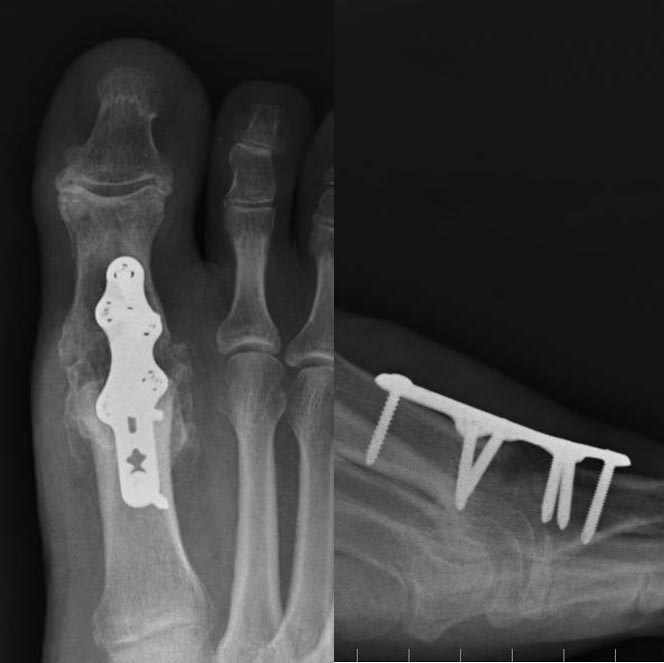

1st MTP Fusion

With a fusion the damaged and worn out joint surfaces are removed using special tools that allow the two bones to be pulled very close. These two bones are then held with a plate and should fuse together to become one. The operation is usually performed through an incision over the top of the joint. The plate and screws are usually left in and cause no problems.

There is a small chance of the bones not fusing together and this is called "non-union". Smoking and diabetes increase this risk. If this happens you may need further operations to deal with the problem. Occasionally the plate and screws can become prominent and need removing through the same incision at a second operation.